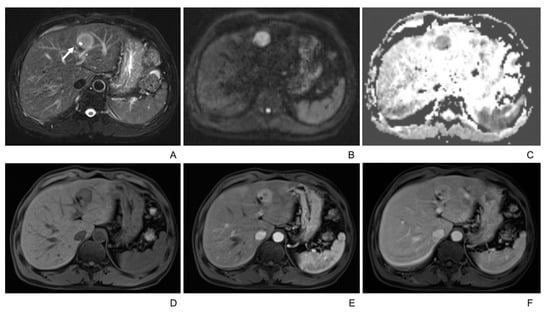

| T2WI | |

| Homogenously intermediate/hyperintense | 8 (21%) |

| Peripheral hyperintensity and central hypointensity | 18 (47%) |

| Heterogeneous | 12 (32%) |

| Isointense/not seen | 0 |

| T2 hyperintense foci | 10 (26%) |

| ADC value of lesions (mm2/s) | 1070 ± 255 |

| ADC value of liver (mm2/s) | 1335 ± 351 |

| p = 0.001 (<0.05) | |